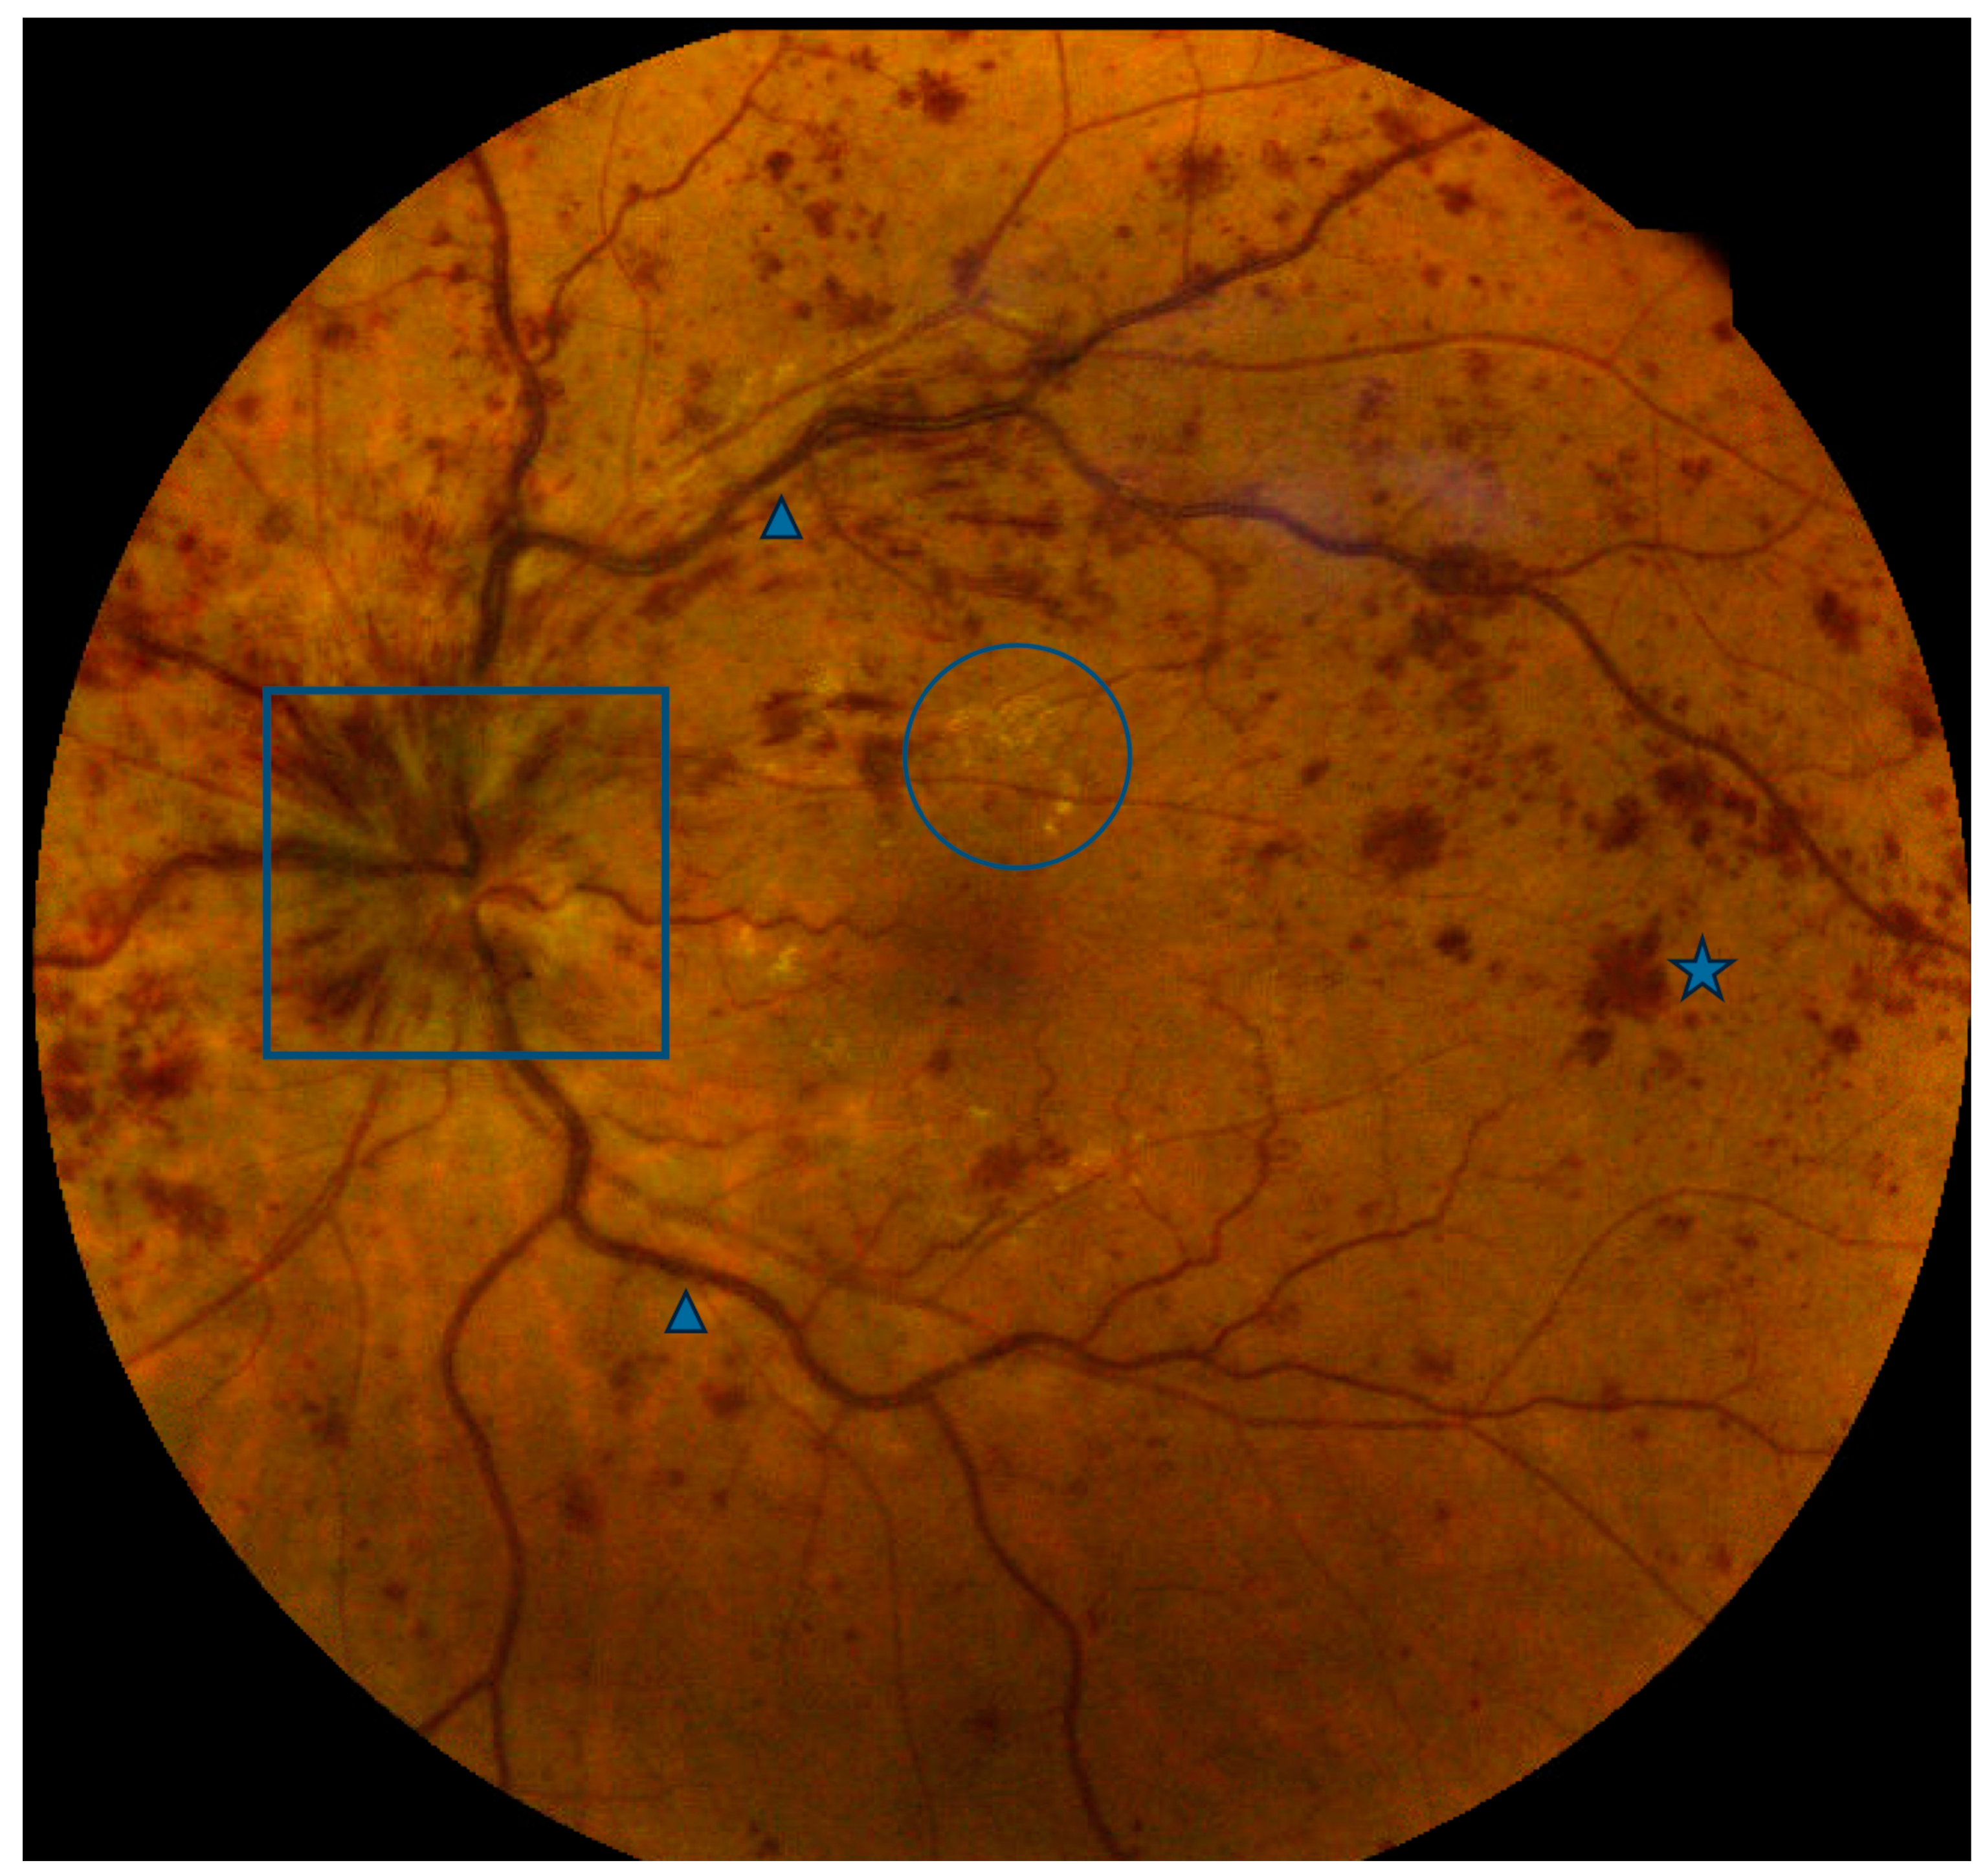

Optical coherence tomography findings known as retinal ischemic perivascular lesions (RIPLs) were recently described in the literature []. RIPLs are characterized by focal atrophy of the inner nuclear layer (INL) accompanied by secondary expansion of the outer nuclear layer, resulting in an undulating appearance of the middle retinal layers (Figure 5). RIPLs are thought to arise at the sites of previous middle retinal layer infarcts, potentially evolving as a subsequent manifestation of paracentral middle maculopathy (PAMM), wherein the hyperreflective inner nuclear band observed during the acute phase gradually undergoes atrophy over time. PAMM has not been conclusively shown to confer increased cardiovascular risk. However, RIPLs do appear to be representative of end-organ infarction secondary to vascular dysfunction and are linked with cardiovascular disease.

Figure 5.

Ocular coherence tomography demonstrating several areas of focal atrophy of the inner nuclear layer (INL) with underlying expansion of the outer nuclear layer consistent with retinal ischemic perivascular lesions (RIPLs) (arrows).

A retrospective study of 160 subjects demonstrated a higher number of RIPLs in individuals with cardiovascular disease and, crucially, found that each additional RIPL identified on imaging conferred greater odds of cardiovascular disease, after adjusting for age, sex, and smoking status []. The presence of 1, 2, or 3 RIPLs was associated with an increased odds ratio of developing CVD of 2.3, 4.2, and 5.3, respectively, after adjusting for multiple covariables. Moreover, patients with intermediate or high 10-year ASCVD (atherosclerotic cardiovascular disease) risk scores were found to have more RIPLs than patients with low or borderline ASCVD risk scores. RIPLs have also been explored as an occult imaging biomarker for systemic cardiovascular disease. In a recent study, 8 of 11 (72.7%) patients with RIPLs and no prior diagnosis of cardiovascular disease were found to have newly diagnosed CVD upon further workup with their primary care physician or cardiologist []. Two of these patients required surgical intervention, including coronary artery bypass graft and carotid artery stent placement, and 3 were started on new medications. Despite the report’s limited sample size, the profound implications of the findings underscore the importance of considering cardiovascular evaluation in patients with RIPLs. These lesions, reasonably considered a new ophthalmic imaging biomarker of cardiovascular disease, may encourage ophthalmologists to refer their patients for age-appropriate cardiovascular disease screening (at minimum, serial blood pressure monitoring, lipid profile, and hemoglobin A1C). Patients in the aforementioned study also underwent electrocardiography and echocardiogram, with carotid duplex and ambulatory ECG also revealing abnormalities, in some cases resulting in invasive cardiac testing or surgical intervention.